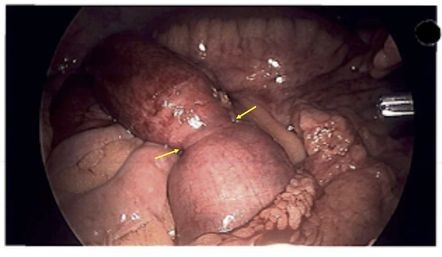

DOR ABDOMINAL E ADERÊNCIAS

As aderências peritoneais pós-operatórias são consideradas complicações inevitáveis e graves após cirurgias como colecistectomia, gastrectomia, apendicectomia, histerectomia, colostomia, ressecção abdominoperineal e procedimentos vasculares abdominais. A incidência de aderência pós-cirúrgica geralmente varia de 67% a 93% após procedimentos abdominais cirúrgicos gerais, chegando a 97% após operações pélvicas ginecológicas abertas. Adesão pós-cirúrgica não só traz enorme ônus financeiro para a família do paciente, como também resulta em muitos problemas, como dor crônica, infertilidade feminina, obstrução intestinal, etc.

BRIDAS E ADERÊNCIAS INTESTINAIS.

Visão histórica de um problema que se mantém atual. Bridas e aderências intra abdominais são lesões já referenciadas nos papiros do antigo Egito. Bem conhecida nos primórdios da patologia no contexto da tuberculose ou outra doença infamatória peritoneal, torna-se comum depois do advento da cirurgia abdominal na segunda metade do século XIX, pela obstrução intestinal que estas aderências pós-operatórias criam. É uma patologia que ainda hoje mantém importante morbilidade. O autor revê a evolução histórica desta doença e apresenta uma imagem dos primórdios do registo gráfico desta patologia.